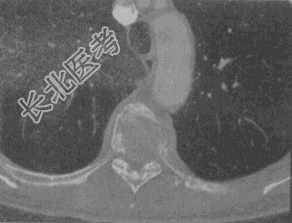

- 单项选择题女,58岁, 背部隐痛2个月余,1年前行乳癌根治术, 结合影像学检查,最可能的诊断

E、脊柱转移瘤